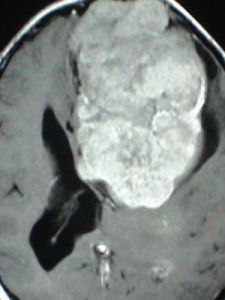

腦瘤後遺症,是指腦瘤經手術切除後而留下的後遺症狀。這些症狀的存在並不是由於腦瘤的存在而引起,因為這時腦瘤已被切除而治癒,後遺症是由瘤體或手術所造成的神經功能受損所致。

在手術切除腫瘤的過程中,往往由於腫瘤組織與腦組織的粘連或手術切除的需要而造成一些腦神經組織的受損,從而產生一些相應的臨床症狀。如出現肢體麻木、疼痛、運動不靈、語言不利等等症狀。不能全部切除的腫瘤,其殘餘腫瘤體的存在將繼續產生對局部腦組織的壓迫而表現出各種不適症狀。如頭痛、頭暈等。這些都是腦瘤術後遺留的後遺症狀,需要通過後期的康復治療來解決腦瘤後遺症。